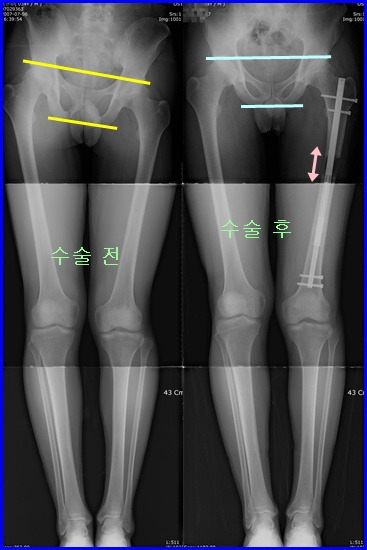

좌측다리가 짧아 내원한 30대 남자 환자입니다. 10대 때에 다리를 다치면서 한쪽다리가 3.5cm 짧아진 환자입니다.

수술 전 엑스레이상 하지부동으로 인한 골반 경사가 심합니다. 평소 절면서 걷고, 요통도 심한 상태였습니다.

ISKD를 이용하여 좌측의 대퇴골을 3cm 연장하였습니다.

수술 후 2개월 째에 거의 완벽하게 교정 되었습니다.